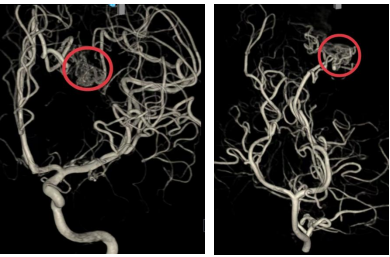

▲DSA提示左侧顶枕叶复杂动静脉畸形,由前后循环分支供血,畸形灶内可见多个小动脉瘤

8月15日凌晨,在麻醉科,第一手术区医护人员的全力配合下,张锟和段练为患儿成功实施了右侧脑室钻孔引流术及颅内压监测探头置入术。术中监测患儿颅内压极高,医生引流血性脑脊液后颅内压下降。手术开始半小时便为患儿搭建了生命通道,术程十分顺利。术后患儿转入重症医学科(ICU),给予机械通气,镇静镇痛,脑保护等治疗,患儿病情趋于平稳。术后第二天,在导管室,神经外科团队为患儿进行了全脑血管造影检查。检查发现患儿为左侧顶枕叶复杂动静脉畸形,由前后循环分支供血,畸形灶内可见多个小动脉瘤,Spetzler分级3级。这个消息让医护人员和患儿家属的心情愈加沉重。